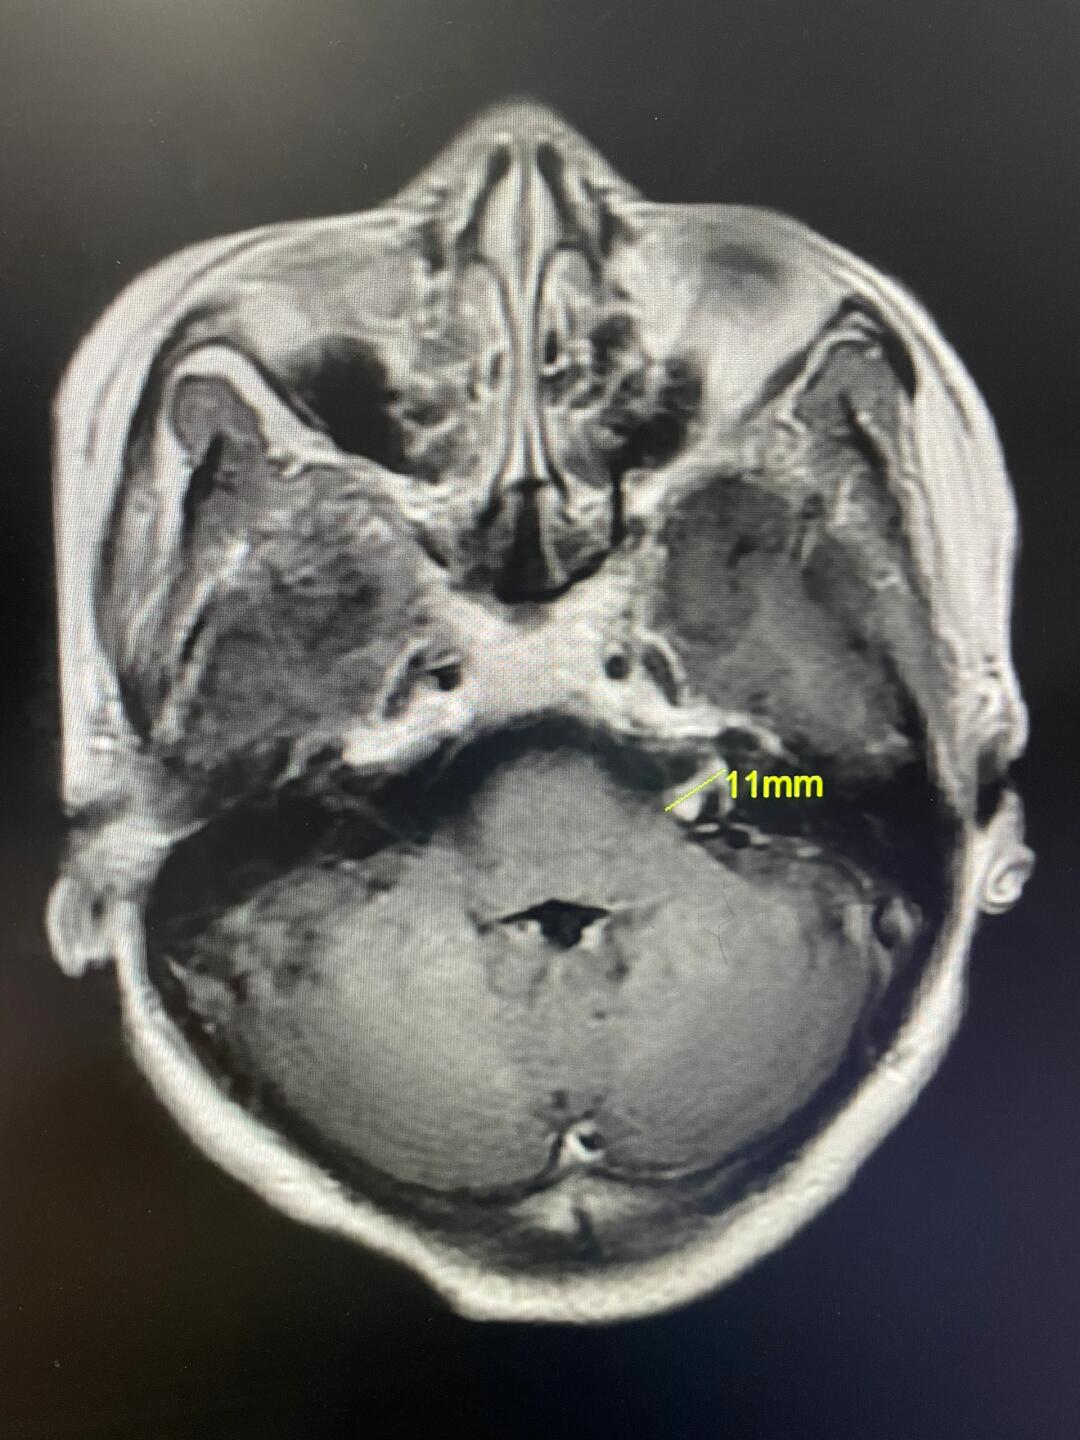

46岁女士——左侧听神经瘤图片